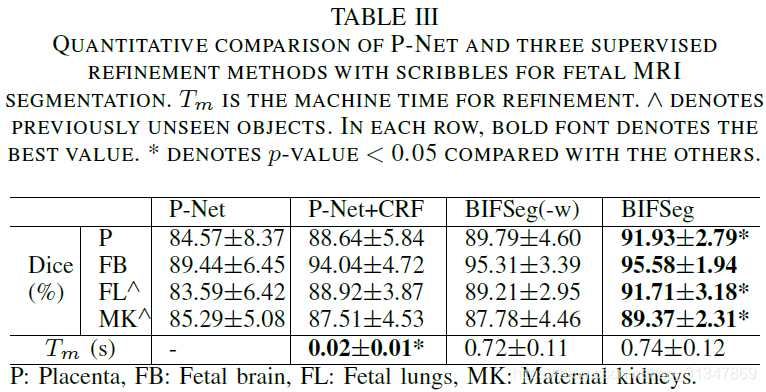

比较 BIFSeg 和 1)P-Net/PC-Net 的初始分割结果;2)用 CRF 处理之后的分割结果;3)BIFSeg(-w) 的分割结果(基于 Eq(1),所有像素的权重 w ( i ) = 1 w(i) = 1 w(i)=1),以及其他交互式分割方法:用于 2D 分割的 GrabCut,SlicSeg,Random Walks;用于 3D 分割的 GeoS,GrowCut,GrabCut 3D

(3)Supervised Image-specific Fine-tuning:

同一个初始分割结果,同样的 scribbles,对比三种调整方法,虽然都有效果上的提升,但依然发现是 BIFSeg 的分割结果最好。

(4)与其他交互式分割方法的比较:

BIFSeg 可以实现花费更少的用户时间,但精度上与其他方法相近或更高。